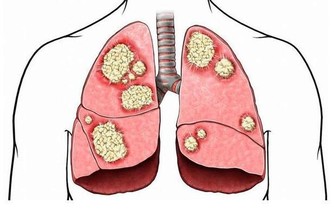

- 自體免疫性疾病:如多發性硬化症或類風濕性關節炎,這些疾病可能攻擊神經系統,導致麻木感。

- 內分泌失調:例如甲狀腺功能異常也會影響神經傳導,從而引發麻木症狀。

對於有慢性疾病史的人群,定期檢查與專業治療非常重要,以避免症狀進一步惡化。